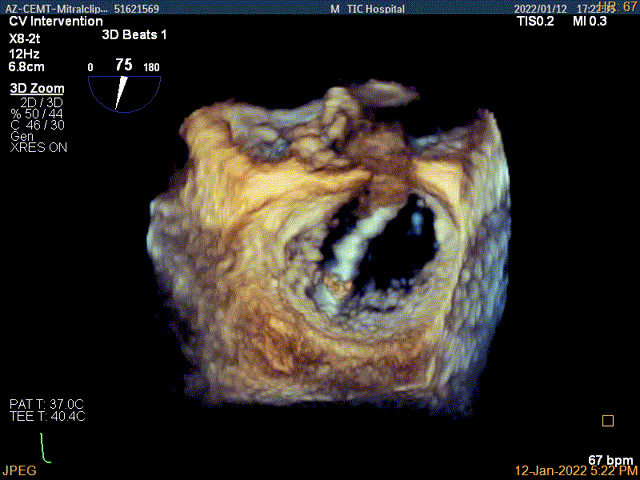

3D MV View:二尖瓣AC区为主(累及部分1区)脱垂并腱索断裂

3D-color MV view:大量返流,主要来源于AC区

TEE Bicom view:二尖瓣AC区为主(累及部分1区)脱垂并腱索断裂。

Color-view:大量返流,主要来源于AC区

3D-color-VIEW验证残余返流来源

3Dview验证两个夹子的位置是否平行

3D-view验证两个夹子位置稳定,排列紧密

3D-Color-view验证微少量残余返流